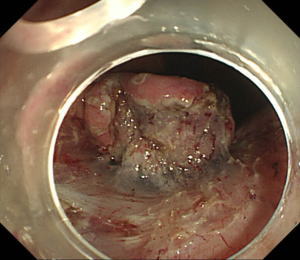

| 【胃ESD】 |

粘膜下層の剥離が進んで早期胃癌が存在する表面の部分(粘膜)が剥がれてきました。 |